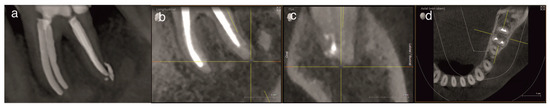

Objective: To report a rare case of pulp space tissue growth in a mature mandibular molar with severe endo-periodontal involvement after conservative endodontic treatment and to discuss the possible biological explanations, including regeneration and granulation tissue healing. Severe endo-periodontal lesions are challenging, particularly [...] Read more.

Objective: To report a rare case of pulp space tissue growth in a mature mandibular molar with severe endo-periodontal involvement after conservative endodontic treatment and to discuss the possible biological explanations, including regeneration and granulation tissue healing. Severe endo-periodontal lesions are challenging, particularly as endodontic regeneration is usually observed in immature teeth, while revascularization in mature teeth, especially in cases of advanced periodontal disease, is rare, as demonstrated in this case. Methods: This study reports a rare case of tissue regeneration versus granulation tissue healing in the pulp space, occurring alongside periodontal healing, in a mature mandibular molar with necrotic pulp and severe periodontal involvement. A 52-year-old patient presented with a mature mandibular molar (tooth #19) exhibiting necrotic pulp with severe endo-periodontal involvement, including grade-3 mobility, tenderness to percussion, a 12 mm probing depth, and extensive periradicular radiolucency. The tooth was diagnosed with necrotic pulp and symptomatic apical periodontitis and was deemed hopeless, with extraction planned. Results: Following patient refusal, endodontic treatment was initiated, including cleaning, shaping, and placement of the intracanal medicament, Ledermix. The patient canceled the extraction due to symptom resolution and disappeared for 12 months. On return, the patient presented with spontaneous pain exacerbated by thermal stimuli, consistent with symptoms of irreversible pulpitis. Clinical examination revealed significant clinical and radiographic improvements, including reduced probing depth (3 mm), no mobility, resolution of apical translucency, radiographic findings suggestive of canal narrowing, and a positive pulp sensibility response. Re-entry elicited profuse bleeding with newly formed vital tissue beneath the medicament. Sodium hypochlorite irrigation failed to achieve hemostasis; inflamed tissue was removed; root canals were cleaned, shaped and obturated; and treatment was completed with placement of a permanent coronal resin composite restoration. A forty-month follow-up showed an asymptomatic tooth with clinical and radiographic healing. Conclusions: This case demonstrates that conservative endodontic management may result in favorable clinical and radiographic outcomes in mature teeth with severe endo-peroidontal involvement, influencing extraction decisions. It provides clinical evidence suggestive of tissue regeneration and periodontal healing in a mature tooth with necrotic pulp and severe periodontal compromise, challenging conventional prognosis. The observed pulp space tissue growth may be suggestive of regeneration; however, alternative explanations, including granulation tissue healing or repair processes, cannot be excluded. Healing by granulation tissue in the pulp space remains possible. Root canal treatment in advanced endo-perio lesions can yield favorable outcomes and may influence extraction decisions. Further clinical and histological studies are needed to clarify underlying mechanisms and optimize treatment strategies. Full article

Show Figures

Figure 1